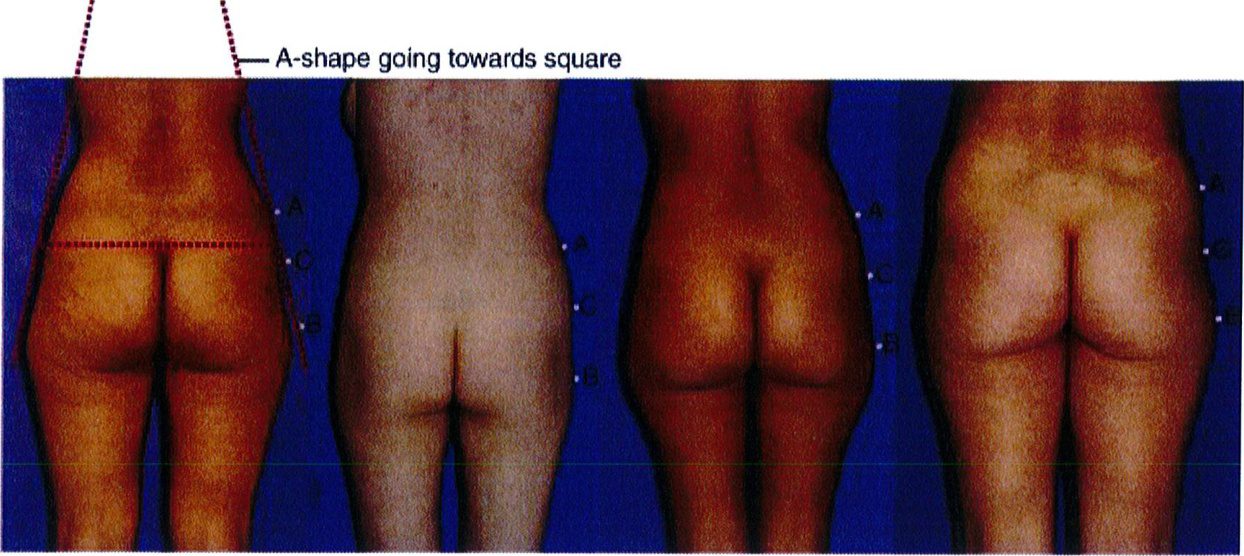

Việc phân loại các loại khung được thực hiện bằng cách so sánh và đối chiếu lượng chất béo có sẵn trong 3 vùng cụ thể. Điểm nhô ra nhất ở vùng hông, giới hạn trên được đánh dấu là điểm A, điểm nhô ra nhiều nhất ở vùng đùi ngoài

là điểm B và điểm giữa mặt ngoài mông là điểm C (Hình 4).

Sự kết nối các điểm A và B ở mỗi bên của cơ thế dẫn tới việc xác định 4 loại khung cơ bản: Hình chữ A, hình chữ V, hình vuông và hình tròn (Hình 5).

Khung chữ A gặp ở khoảng 30% bệnh nhân. Khi nối các điểm A và B, tạo ra hình dạng gần như chữ A (Hình 11). Hình dạng này đặc biệt vì chúng tích nhiều mỡ ở hơn ở vùng đùi ngoài phía trên (điểm B) và ít chất béo hơn ở vùng hông bên (điểm A). Lý tưởng nhất là điểm A nhô ra nhiều hơn một chút. Lúc này, khi rút chất béo ở điểm B đi, mông bắt đầu có dạng vuông. Điểm C có thể bị lõm đi nhiều, song ở dạng này hầu hết các trường hợp chỉ lõm mức nhẹ hoặc trung bình.

Khung chữ A gặp ở khoảng 30% bệnh nhân. Khi nối các điểm A và B, tạo ra hình dạng gần như chữ A (Hình 11). Hình dạng này đặc biệt vì chúng tích nhiều mỡ ở hơn ở vùng đùi ngoài phía trên (điểm B) và ít chất béo hơn ở vùng hông bên (điểm A). Lý tưởng nhất là điểm A nhô ra nhiều hơn một chút. Lúc này, khi rút chất béo ở điểm B đi, mông bắt đầu có dạng vuông. Điểm C có thể bị lõm đi nhiều, song ở dạng này hầu hết các trường hợp chỉ lõm mức nhẹ hoặc trung bình. Dạng khung này thường được cải thiện khi hút mỡ ở điểm B hoặc vùng đùi bên (Hình 12). Điểm C có thể cần ghép mô mỡ, tùy thuộc vào mức độ lõm. Nên tránh hút mỡ quá nhiều ở điểm B để ngăn chặn điểm lõm ở khu vực này, ngẫu nhiên hình thành ranh giới giữa vùng mông và mặt ngoài đùi.

Dạng khung này thường được cải thiện khi hút mỡ ở điểm B hoặc vùng đùi bên (Hình 12). Điểm C có thể cần ghép mô mỡ, tùy thuộc vào mức độ lõm. Nên tránh hút mỡ quá nhiều ở điểm B để ngăn chặn điểm lõm ở khu vực này, ngẫu nhiên hình thành ranh giới giữa vùng mông và mặt ngoài đùi.

Hình. 11. Hình minh họa khung dạng chữ A với mức độ lõm nhẹ, trung bình và nhiều ở điểm C. Điểm A nên là điểm lồi ra nhiều nhất của vùng mông ở dạng này, nên sẽ thực hiện hút mỡ ở điểm B để cân đối lai.